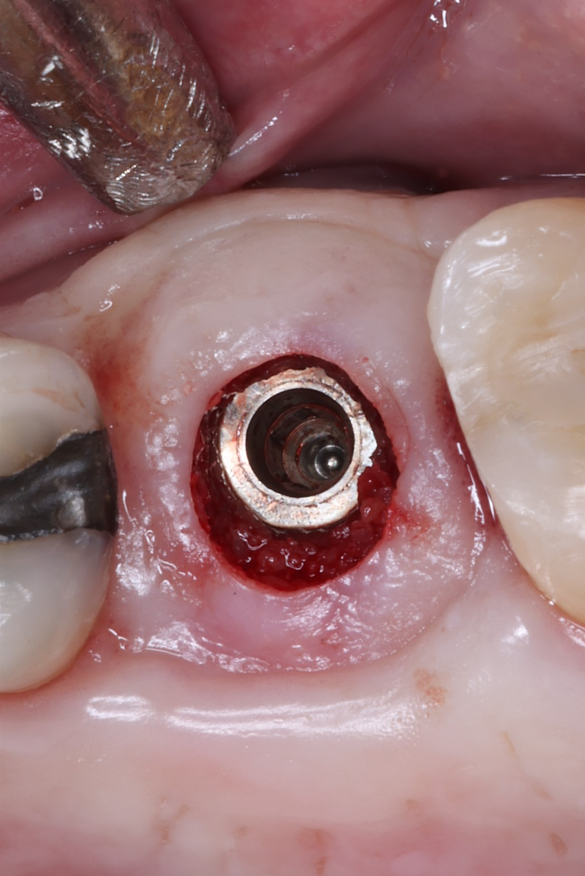

Today, we placed the implant, scanned for the final restoration, just like teaches us to do, and I placed a Neodent healing abutment.

Couple things about this case, I chose to do a tissue punch because the width of the ridge and the amount of attached tissue present. When we use the PTFE membrane for socket preservation, we ultimately grow nice, thick attached tissue, and this is a perfect example of that. I probably only do one or two tissue punches a year.

Notice in the final pictures, the amount of attached tissue is greater around the implant that it is around the natural teeth. Bone is obviously important for implants, but attached tissue will determine how long they last and how healthy they stay.